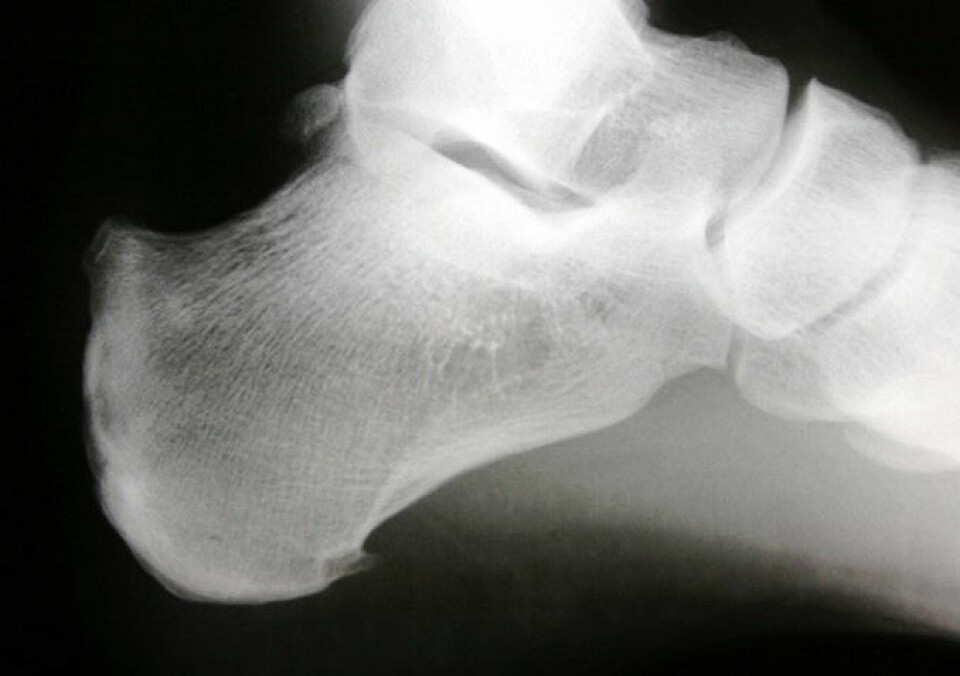

Spiss: Vi ser en typisk spiss i hælen, av Haglunds type. (Foto: Odd Arne Daljord)